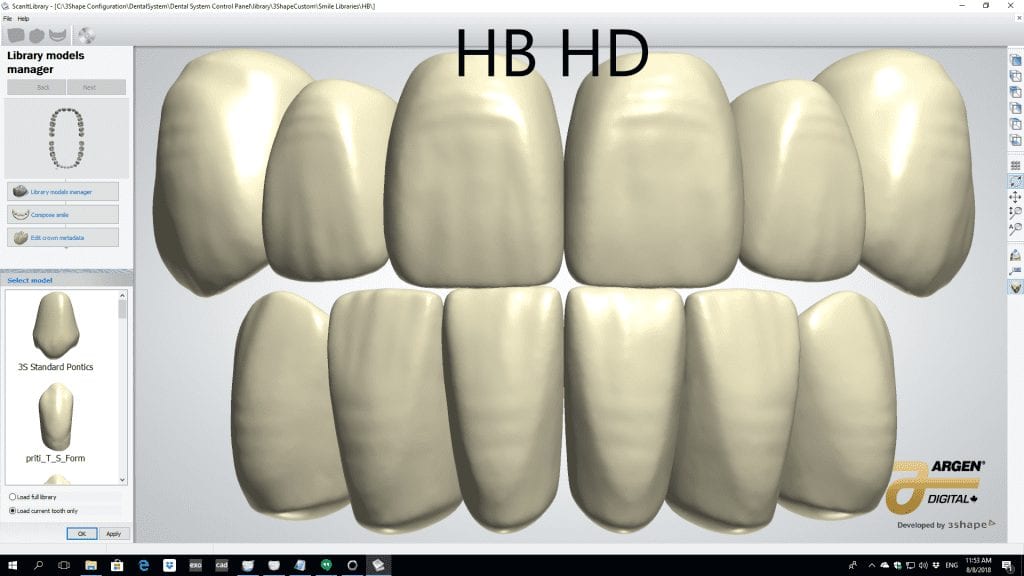

The digital models were then imported into a third party software where a library of tooth morphologies are available for the clinician to choose from.

Once the appropriate library is chosen, the digital wax ups are performed. In the subsequent photos you can see the transparent overlay of the wax-ups to the original position of the existing dentition